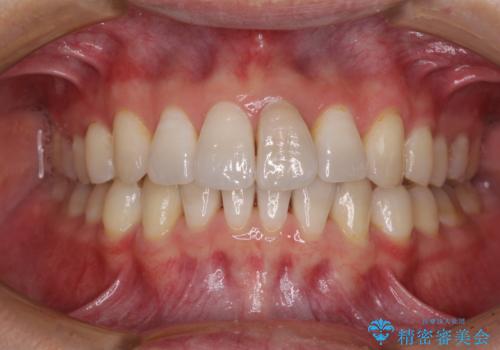

- 前歯の出っ歯と口元の閉じにくさを気にして来院された患者様です。

口元を積極的に引っ込めるために、上下左右の小臼歯4本を抜歯することとしました。

4本の歯を抜歯したことで、飛び出していた口元が引っ込み、横顔が大きく改善されました。

咬み合わせが悪化することのないようにスペースを閉じていくことができ、比較的スムーズに治療を進めることができました。